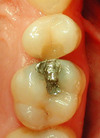

- Cas 2 : 1 prémolaire et 1 molaire supérieures - 1 séance de 90 minutes